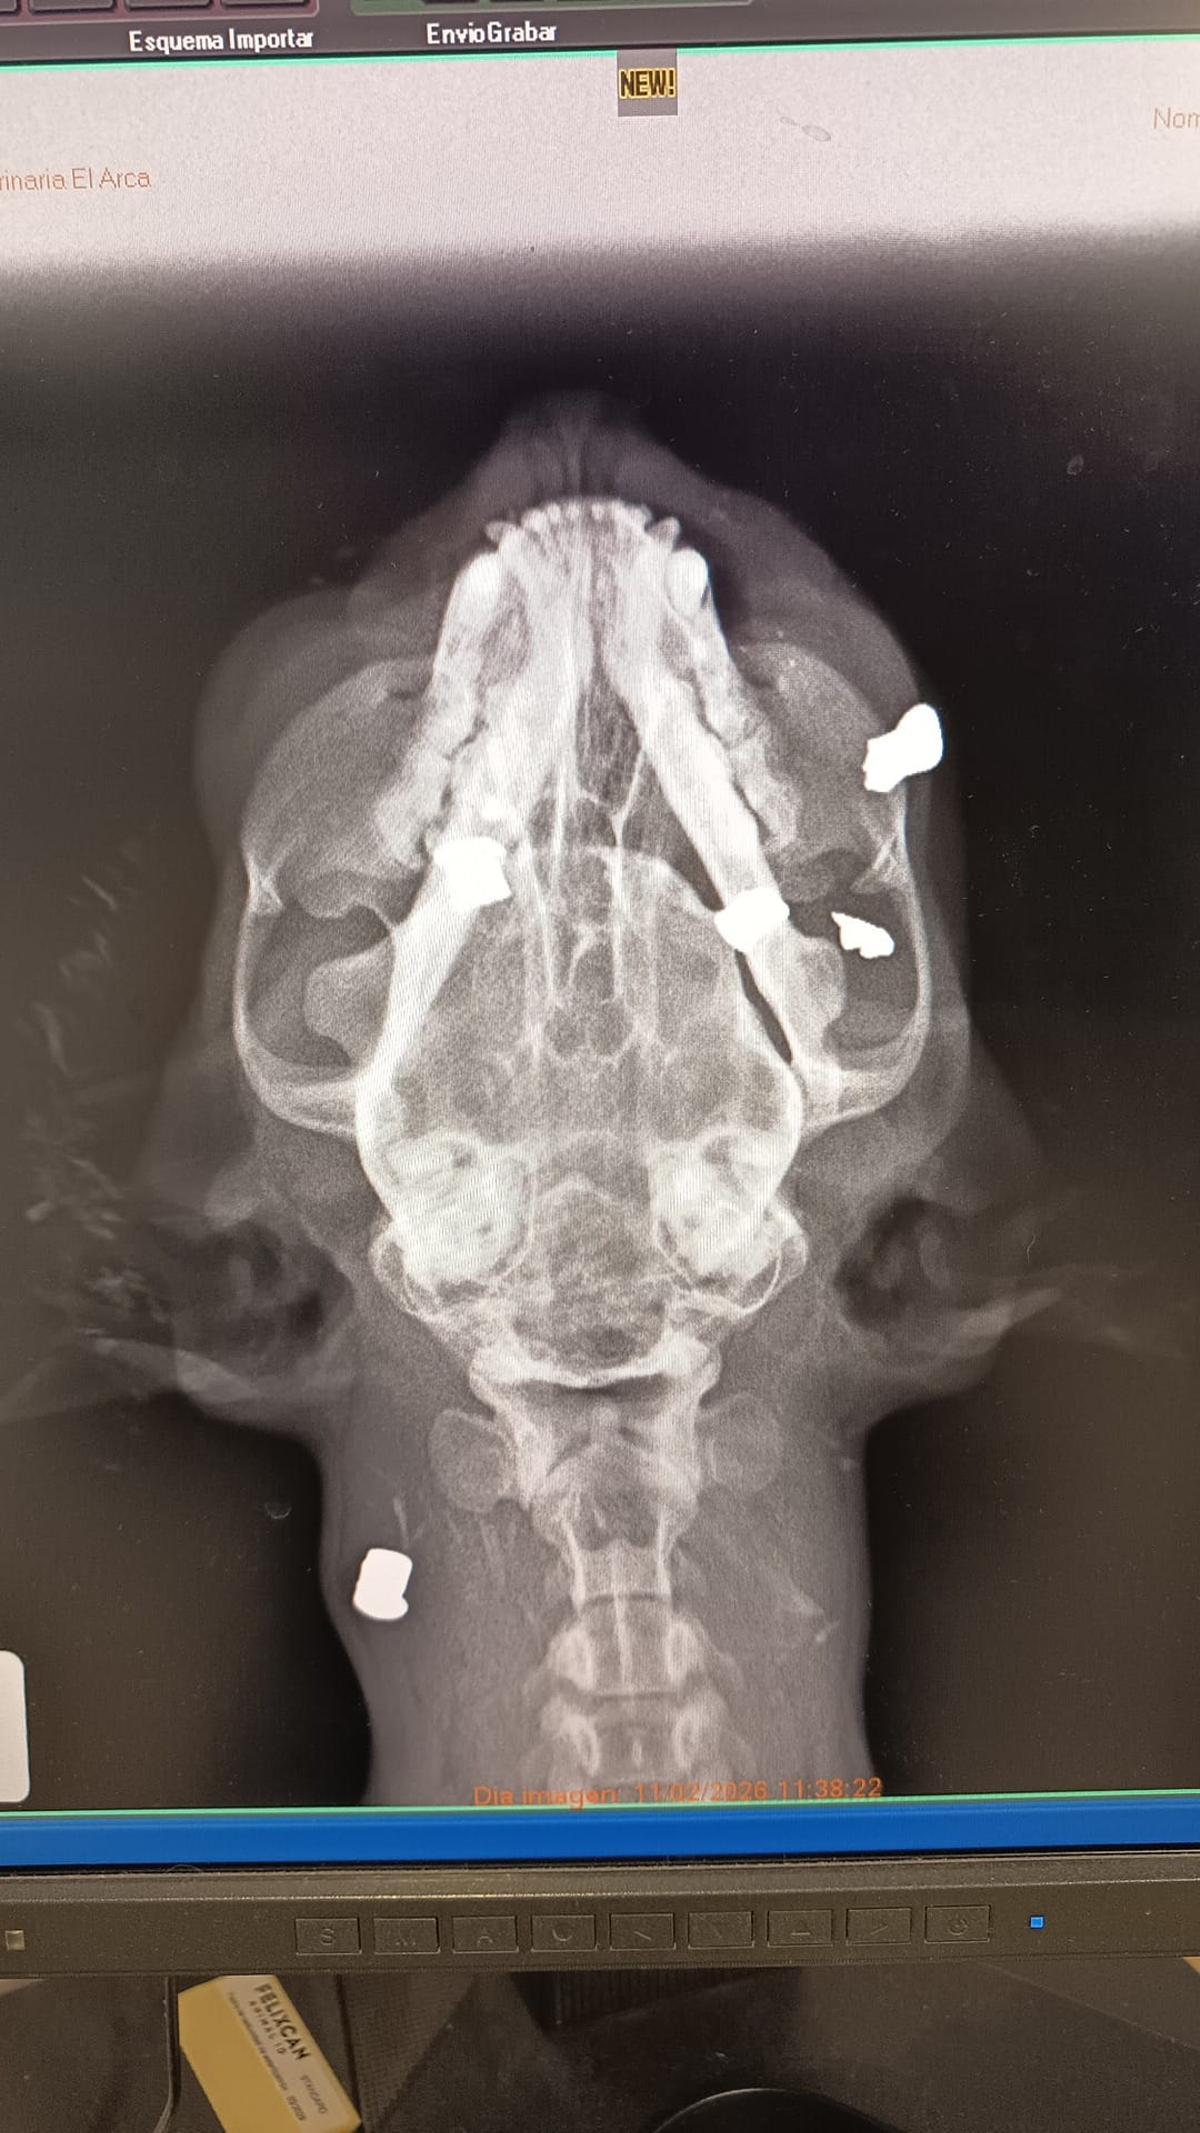

Radiografía donde se aprecian los perdigones dentro del cuerpo de la gata. / INFORMACIÓN

La Protectora fue alertada del hallazgo y recogió a la gata, que estaba embarazada y presentaba cinco balines en su cuerpo. El animal fue llevado a una clínica veterinaria, donde estimaron que podría llevar más de un día herida desde que recibió los disparos. La gata quedó ingresada en la clínica veterinaria y murió al día siguiente a causa de las lesiones sufridas.